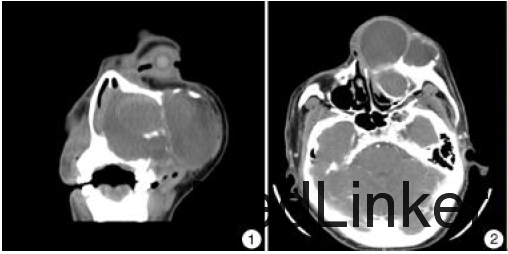

入院查体:左侧鼻背及颌面部明显隆起,触之波动感;鼻骨及鼻腔外侧壁受压变形,左鼻腔狭窄,左侧硬腭局部膨隆凸起,左侧上列尖牙齿龈增生,眼球活动不受限,无明显复视及视力下降。增强CT扫描见左侧牙槽骨、上颌骨团状异常密度影,呈多囊改变,可见分隔,内部见液性平面;囊壁可见钙化,增强后可见强化,内部未见强化;左侧上颌窦窦腔明显受压变形,病变累及左眶内侧壁、鼻腔外侧壁及左侧硬腭,向外累及颞下窝(图1、2)。入院后完善检查,经上颌窦穿刺抽出暗褐色液体约80 ml,诊断为左上颌骨牙源性囊肿。